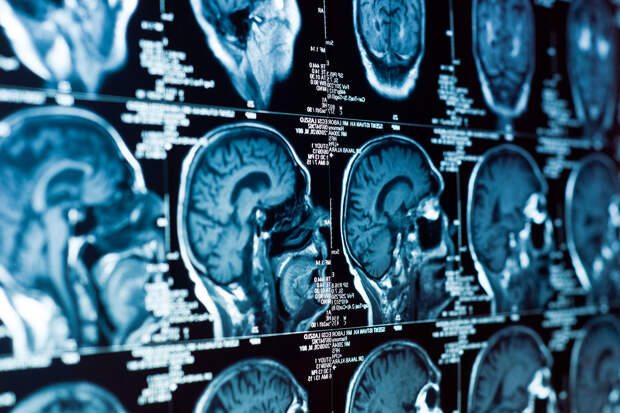

Болезнь Альцгеймера нарушает циркадные ритмы клеток мозга, ответственных за его очищение от токсичных бляшек. К такому выводу пришли ученые из Медицинской школы Вашингтонского университета выяснили. Исследование опубликовано в журнале Nature Neuroscience (NatNeuro).

Эти симптомы давно связывали с нарушением биологических часов, но механизм оставался неясным.Команда под руководством невролога Эрика Мюзика обнаружила, что амилоидные бляшки — ключевой признак болезни — нарушают работу сотен генов, регулирующих суточные ритмы микроглии и астроцитов. Эти клетки выполняют роль "санитаров" мозга: микроглия очищает ткань от токсинов и мертвых клеток, а астроциты поддерживают работу нейронов.

В экспериментах на мышах исследователи показали, что при накоплении амилоида привычные ритмы активности генов в этих клетках сбиваются, превращая упорядоченную систему в хаотичную. В результате нарушается синхронная работа механизмов, отвечающих за выведение амилоида. Более того, амилоид создает "новые ритмы" у сотен других генов, связанных с воспалением.